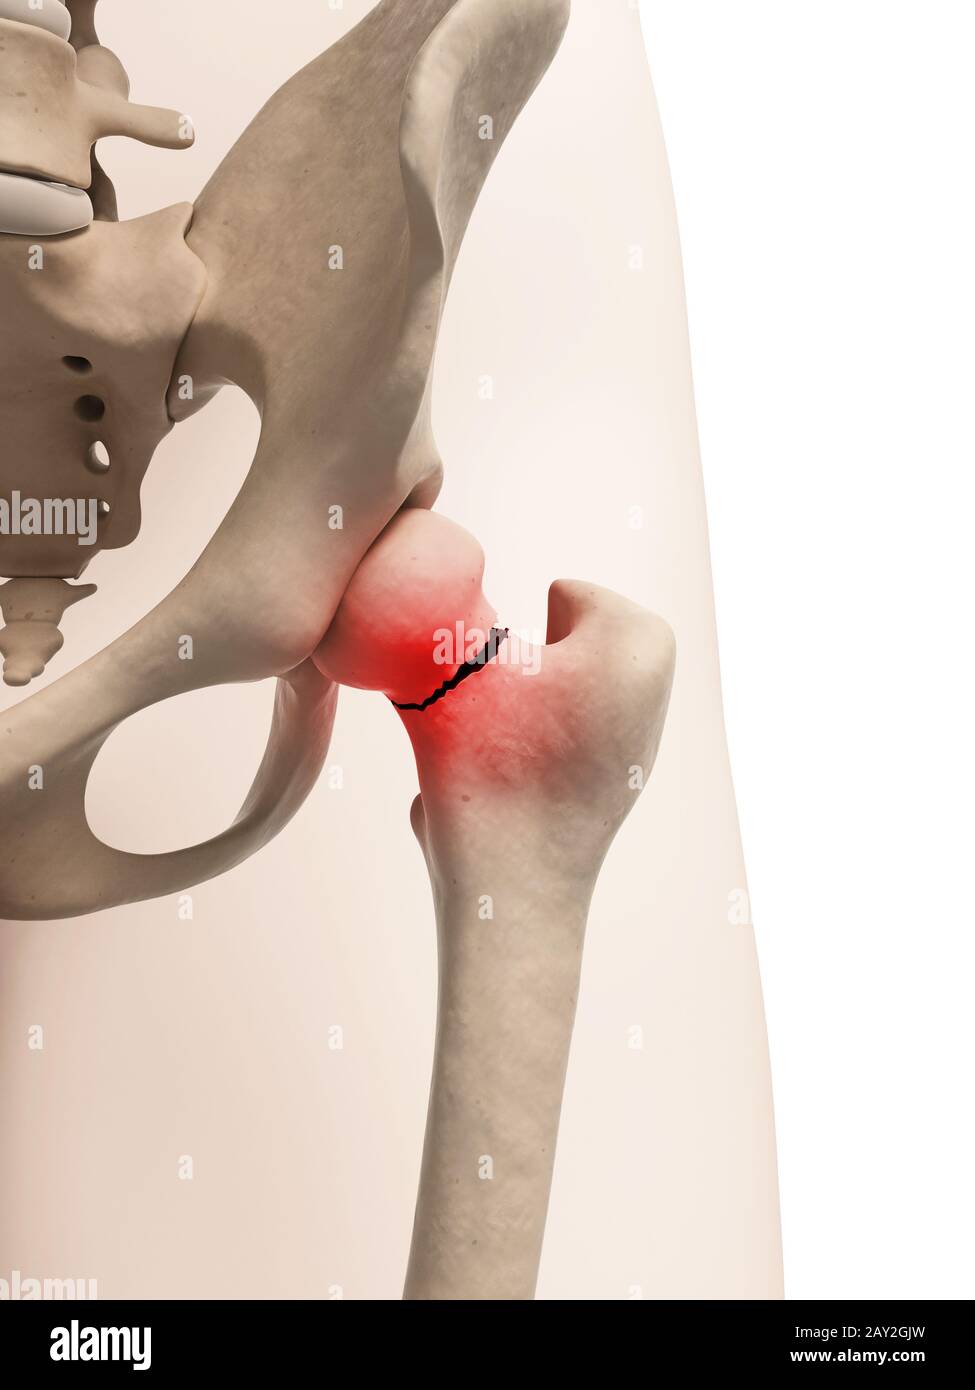

Шейка таза перелом

Шейка таза перелом 111 фото